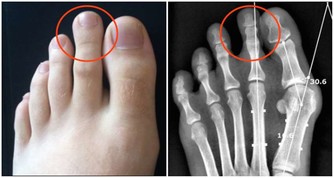

在德克薩斯州旅行結束後,Bill決定要仔細檢查一下自己的肺,畢竟他是一位有著55年菸齡的老煙民。在找到梅奧診所健康系統肺科的Adel Zurob醫生,醫生了解情況後建議Bill做一項肺癌篩查(低劑量CT)。檢查結果顯示:右肺有一個小的癌變結節。通過進一步的正電子發射斷層掃描(PEC-CT),顯示肺部以外沒有擴散或轉移的徵象。醫生建議,立即進行手術治療。